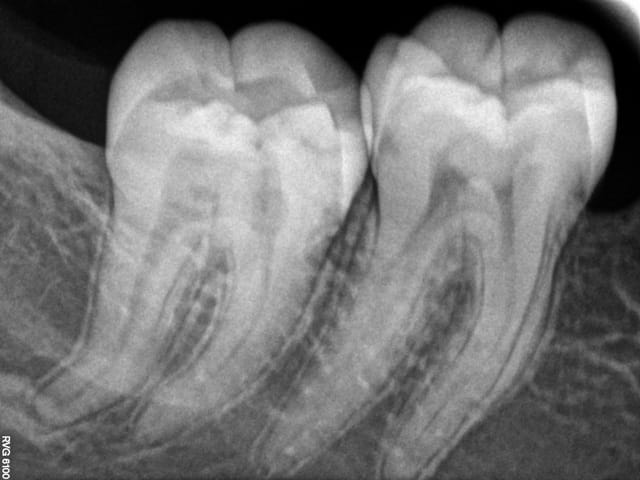

Patiente de 21 ans, 47 sensible à la pression mais pas au froid, avec cette image à l'apex.

A vos avis, qu'est-ce que c'est ?